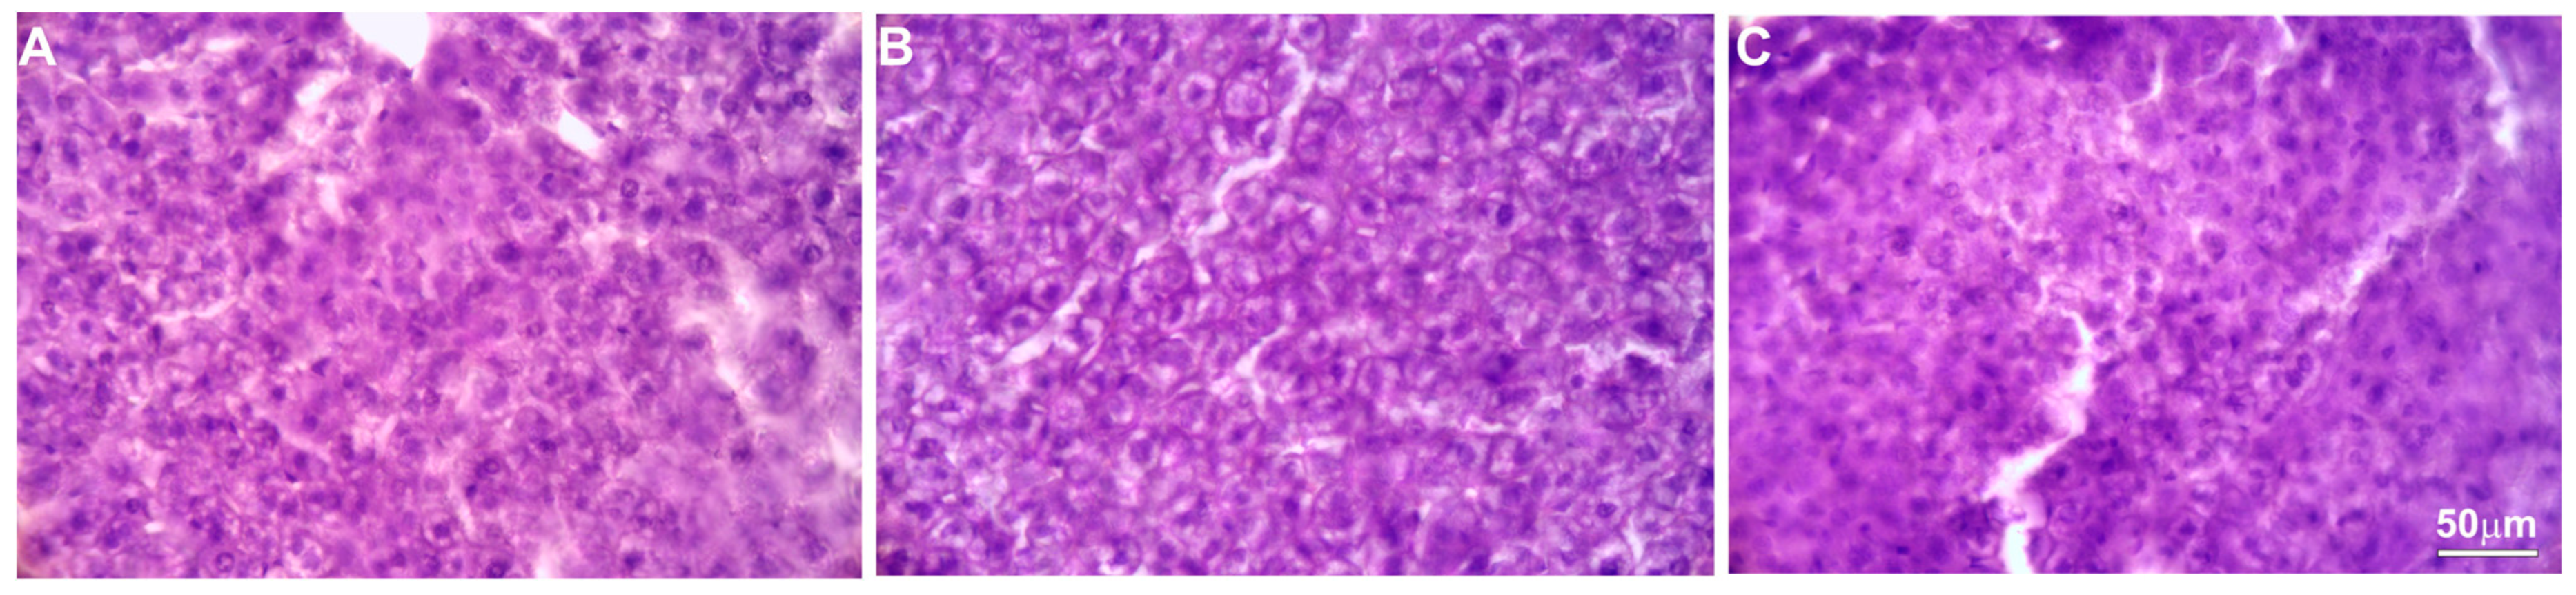

Histopathological evaluation did not reveal any pathological changes in the livers obtained from either the control animals or those obtained from the animals treated with the various concentrations of the intractum. The cells showed proper morphology and architecture, and the livers had a normal tissue structure.

Only in two of the five mice tested were single areas of brighter H and E labelling observed, but the cells in these areas showed no signs of degeneration and had proper morphology and arrangement (Figure 5).

Figure 5.

H&E staining. Microphotographs of representative liver sections obtained from control mice (A) and animals treated with 750 (B) or 1500 mg/kg b.w. (C) of the intractum.

The results obtained clearly showed that the high dose of intractum used did not have a negative impact on the activity of liver cells. The intractum did not exhibit any hepatotoxic activity on liver parenchyma cells, taking into account both the results of blood parameters and histopathological examination. However, high doses of the extract administered to mice induced some changes in blood plasma parameters.

Regarding histopathological effects on the liver, applying various doses of E. senticosus intractum confirmed our assumption that it does not cause a hepatotoxic effect, as we did not observe any liver damage. This confirms reports about the safety of using ES in ethnomedicine. Additionally, [25] reported that the combination of metformin treatment with the administration of ES water extract (200 mg/kg b.w.) contributed to relieving diabetes symptoms and reversing liver and kidney damage to normal levels compared to administering metformin alone in diabetic rats, with along with improvement of blood parameters and body weight. ES extracts not only do not have a negative effect on hepatocytes, but can also protect the liver against deposition of heavy metals such as cadmium (administration of 3.5 mL/L ES stem water extract) [26].